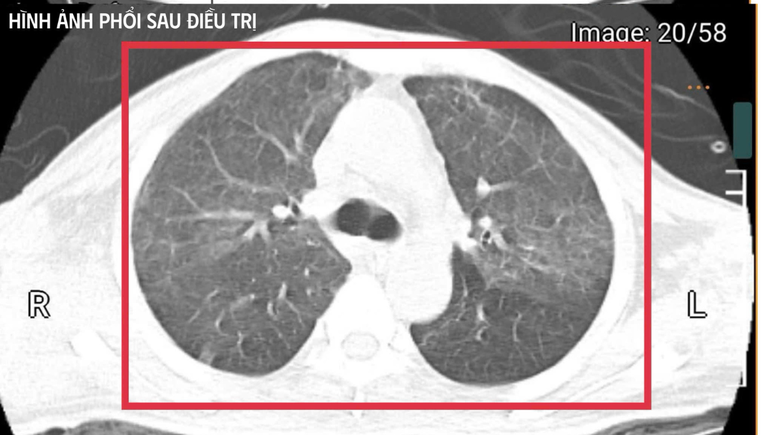

Hình chụp phổi của bệnh nhân sau điều trị

Sau khoảng ba ngày hồi sức cao độ, những tín hiệu sống đầu tiên dần trở lại: cắt sốt, chỉ số viêm giảm dần, huyết áp ổn định hơn, nhu cầu vận mạch giảm, chức năng gan thận cải thiện, tri giác phục hồi. Anh T. dần cai được thở máy qua mở khí quản, tập hô hấp tự nhiên và phục hồi vận động.

Trong ba tuần điều trị tích cực tại Khoa Cấp cứu, các bác sĩ tối ưu kháng sinh, kiểm soát đường huyết, hỗ trợ dinh dưỡng và phục hồi chức năng sớm. Bệnh nhân tiến triển từng ngày và tỉnh táo hoàn toàn. Anh đủ điều kiện xuất viện và tiếp tục theo dõi ngoại trú.